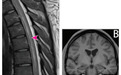

脊髓 T2 加权 MRI 见图 1A,颅脑 T1 加权 MRI 见图 1B 考虑什么诊断?

入院脊髓 MRI:脊髓存在广泛纵向高信号;颅脑 MRI 无异常。因为 CSF 未发现病毒感染迹象,初始诊断为「非感染性脑膜脑脊髓炎」,给予大剂量静脉注射甲泼尼龙治疗。

但 6 个月随访时,患者四肢轻瘫持续存在,并出现新的认知功能障碍(注意力和集中力)。复查 MRI:原多节段脊髓病变消退(图 2A),新增双侧小脑脚、导水管周围病变,轻度至中度全脑萎缩以及严重的双侧海马体积缩小(图 2B)